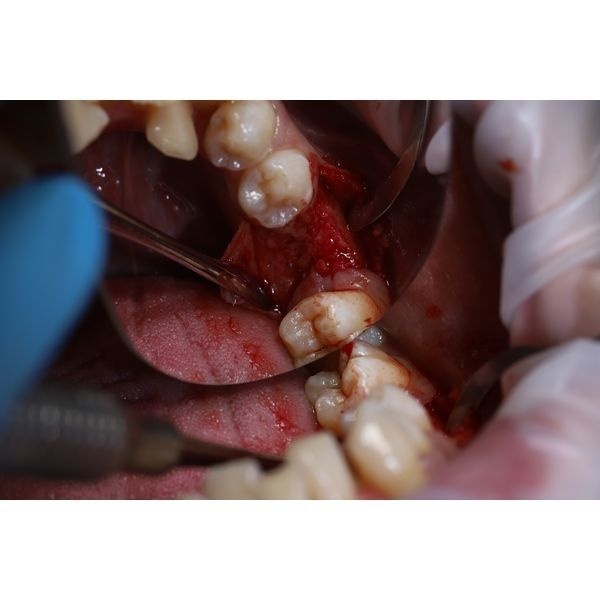

- разрезали ткани в области отсутствующего зуба и откинули слизисто-надкостничный лоскут;

- подготовили имплантационное ложе с помощью фрез;

- установили имплантат Impro 5 × 10 и формирователь десны;

- ушили рану нитями Resolon 5.0;